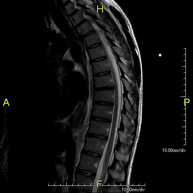

- RM Columna dorsal

Prueba diagnóstica no invasiva que consiste en la obtención de imágenes de alta definición anatómica de la columna dorsal, mediante el empleo de un campo electromagnético y ondas de radio (con un emisor y un receptor). No utiliza radiación ionizante. Indicaciones: traumatismo, problemas degenerativos, hernias, tumores.

Prueba diagnóstica no invasiva que consiste en la obtención de imágenes de alta definición anatómica de la columna dorsal mediante el empleo de un campo electromagnético y ondas de radio (con un emisor y un receptor). No utiliza radiación ionizante. Indicaciones: traumatismo, problemas degenerativos, hernias, tumores.